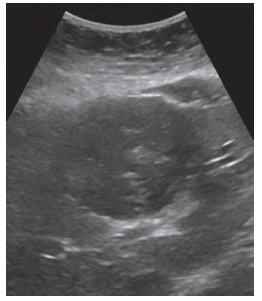

A 38-year-old Iraqi woman with known hydatid cysts presented to the emergency department with a 2-week history of worsening malaise, nausea, fatigue, and jaundice. Echinococcus was established 3 months prior, while during work-up for abdominal pain, and ultrasound revealed 2 hydatid cysts measuring 7.4 cm × 6.7 cm and 6.7 cm × 5.2 cm (Figure 1 and Figure 2). Laboratory studies indicated positive echinococcus IgG enzyme-linked immuno­sorbent assay with confirmatory Western blot. The patient was initiated on albendazole 400 mg twice daily and remained well for a month before her presentation to our facility. On presentation, she was found to have abnormal chemistries with elevated aspartate aminotransferase (AST) 1705 IU/L, alanine aminotransferase (ALT) 2118 IU/L, total bilirubin 5.0 mg/dL, and international normalized ratio 1.3. An examination revealed jaundice and scleral icterus, with no asterixis and normal mentation. She was admitted for expedited work-up of acute liver injury and albendazole was discontinued.